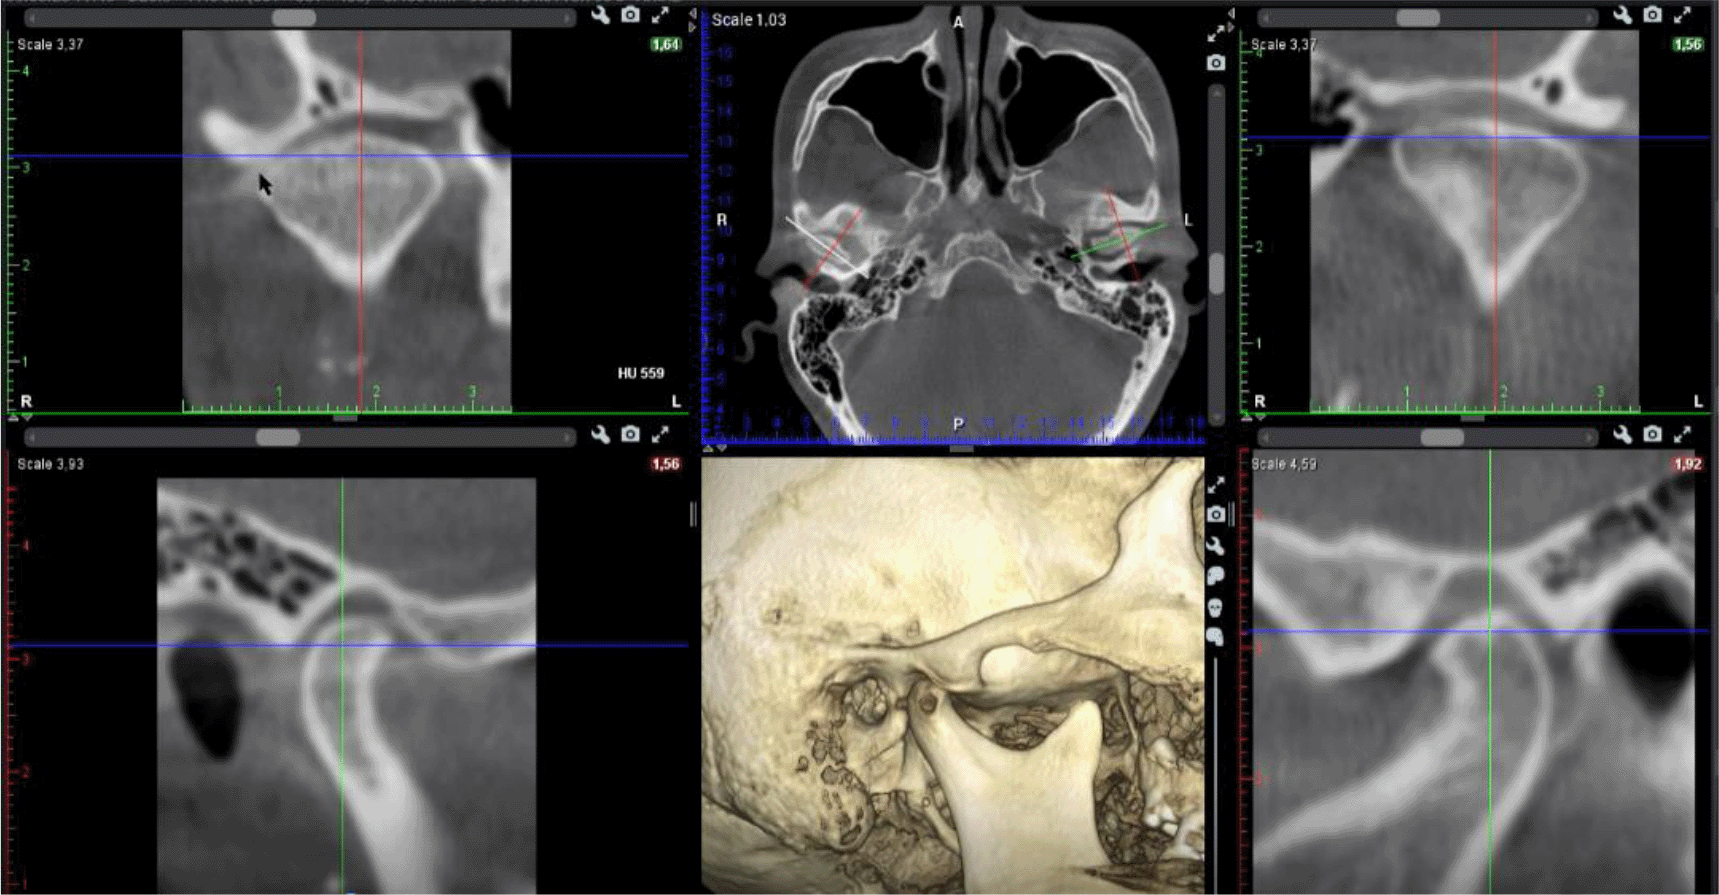

A cone beam CT (CBCT) scan showed an intra-articular problem in the right TMJ. The processus condylaris mandibulae had a preserved convex shape, but its lateral side was in contact with the eminentia articularis. The joint gap between these structures was asymmetric - wider medially and narrower laterally. In the medio-distal direction, the articular condyle was positioned more distally than the normal physiological position. The presence of osteophyte laterally was also established. The left TMJ did not show deviations from the norm (Figures 5 and 6).

26dd931c-41d3-478d-bec1-8cb211d0a4b8_figure5.gif

Figure 5. CBCT visualization – right and left TMJ.

26dd931c-41d3-478d-bec1-8cb211d0a4b8_figure6.gif

Figure 6. Right TMJ condition with osteophyte.